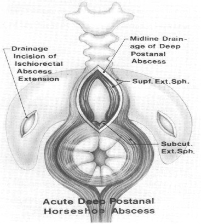

Horse Shoe Fistulas

Horseshoe fistulas are deep posterior anal fistulas which extend into the ischiorectal space with either unilateral or bilateral extensions in the shape of a horseshoe.